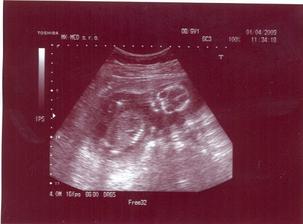

Prvá poradňa bude 2.3.2009. V Poradni všetko OK. UTZ u Dr. Čunderlíka 4.3.2009. Všetko v norme (chvalabohu). Zmenili mi TP zo 4.9.2009 na 13.9.2009. Ďalšia poradňa bude 1.4.2009. V poradni všetko OK. Už len ako dopadnú výsledky z genetiky (7.4.2009). Držte prosím všetci palce. Huráááááááááá AFP testy po opakovaní vyšli super. Konečne budeme mať pokoj. Fuj to bolo dosť zlé ale je to za nami. Už sa len tešiť na bábulko 🙂. Ďalšia poradňa bude 4.5.2009. Snáď uvidíme výbavu 🙂. 25.4.2009 som cítila prvý pohyb (zatiaľ len jeden) 🙂. 29.4.2009 bolo pohybov viacej 🙂)))))). V poradni všetko OK. Asi to bude dievčatko 🙂)))))))))))))))))))))))))). Snáď budem múdrejšia 6.5. 2009 na morfológii. Takže dievčatko to teda nebude 🙂))). Je tam pipík ako hrom. Tešíme sa na Teba synček!!! 20.5.2009 idem na glukózové testy, či nemám tehotenskú cukrovku. Dúfam, že to bude negatívne. Ďalšia poradňa bude 1.6.2009.